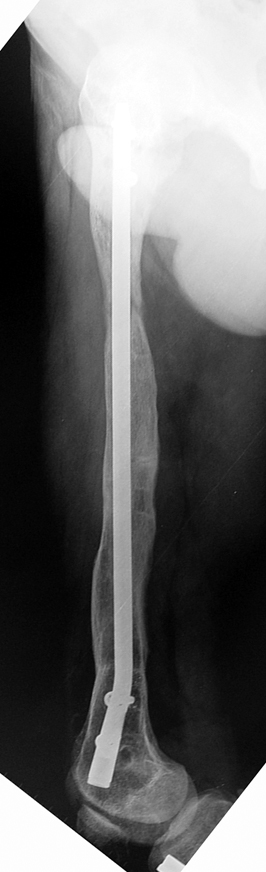

Because the deformity caused by hypophosphatemic rickets is very close to the growth plate, a significant deformity and malalignment occurs. For that reason, more than one deformity centers (CORA) are found at preoperative evaluation, and osteotomy at more than one level is required to correct the deformity. The most frequently used methods to correct the deformity are acute or gradual deformity correction using the Ilizarov method or unilateral external fixator. In the ‘fixator assisted nailing’ technique, which is applied in our department, the deformity is corrected in an acute fashion with the help of an external fixator, and the extremity is stabilized by an intramedullaru nail. The external fixator is removed before the end of the surgery if no gradual lengthening is planned postoperatively. If lengthening (over nail) is planned, the fixator is removed after the completion of the lengthening procedure. As a result, the risk of pin tract infection is eliminated, correction loss and relapsing of the deformity (which are important problems in the treatment of hypophosphatemic rickets) are avoided, eary motion and full weight bearing are allowed, and comfortability of the patient is improved because the duration with external fixator is decreased.

Case 1